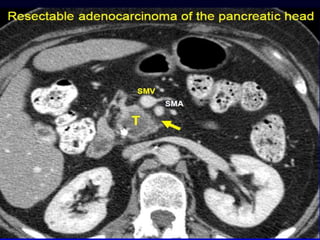

CT

 “Pancreatic protocol CT” is the gold

standard of investigation to stage the

disease and assess the operability

 Triple phase CT

 Closer cuts

 Water used as an intraluminal contrast

 Helical or multislice

 Focal or diffuse mass lesion which is hypo

dense (low attenuation) and hypo vascular

(poor contrast enhancement)

 Dilated MPD and CBD

Vascular

involvement

 Resection of SMV is

accepted provide it

enables to perform R0

resections

 Involvement of SMA is

a contraindication for

resection